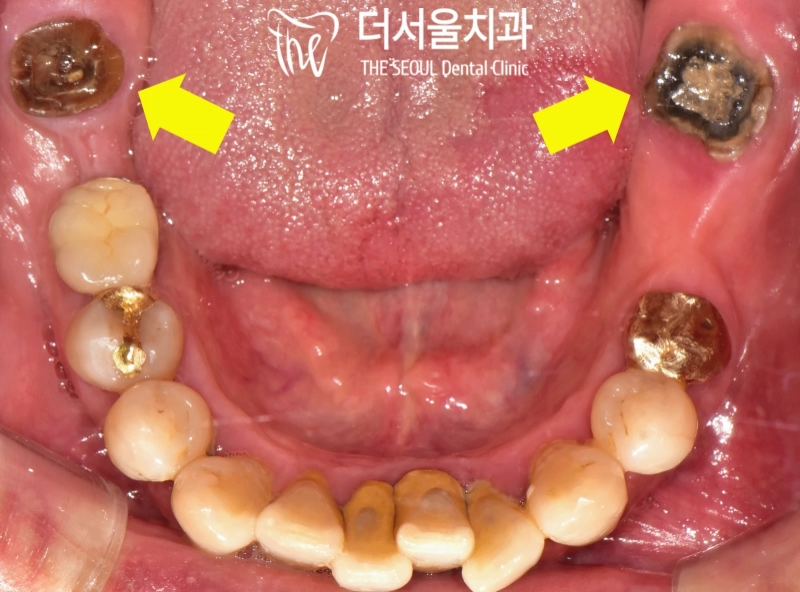

반갑습니다. 잠실 더서울 치과 입니다. 오늘 소개해 드릴 사례는 예전에 찾아오셔서 좌측 아래 어금니 임플란트 식립을 받으셨던 환자분께서 우측